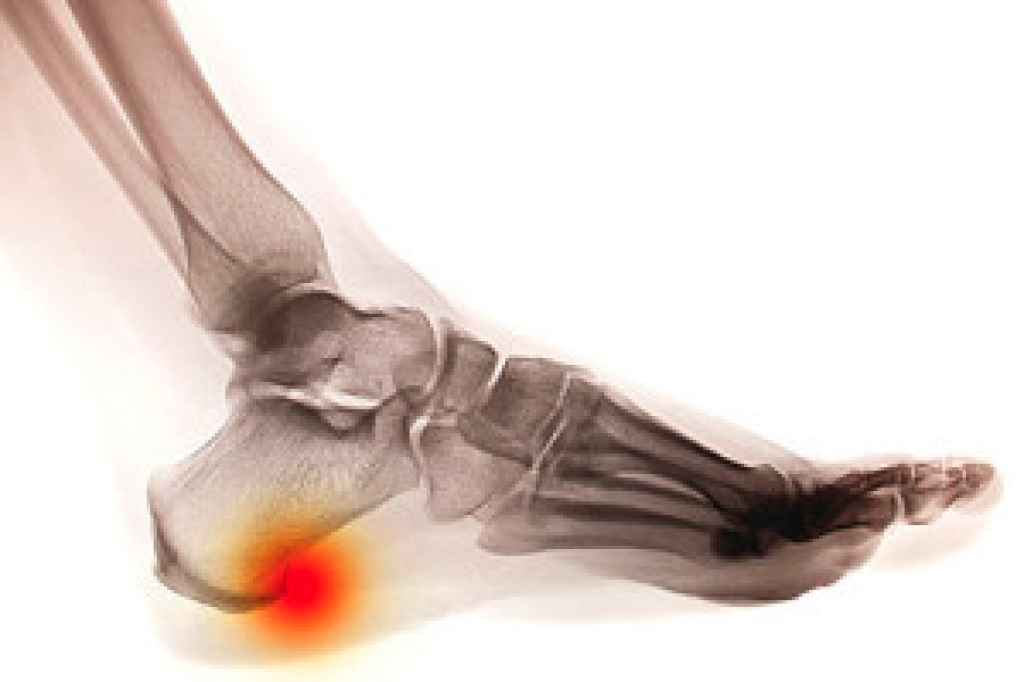

Stress fractures are very thin cracks in a bone. They are often called hairline fractures because of their thin, hair-like appearance. These fractures are typically caused by overuse. Symptoms may include pain which develops gradually in a generalized area, swelling, tenderness, and difficulty bearing weight on the affected foot. A podiatrist can diagnose a stress fracture through a physical examination and X-ray, MRI, or bone scan. Stress fractures are particularly common among runners, basketball players, and ballet dancers. A stress fracture in the foot can affect any of the foot bones, but is usually found on the metatarsal, navicular, calcaneal, medial malleolus, or talus bones. If you suspect that you may have a stress fracture, please seek the care of a podiatrist.

Stress fractures occur in the foot and ankle when muscles in these areas weaken from too much or too little use. The feet and ankles then lose support when walking or running from the impact of the ground. Since there is no protection, the bones receive the full impact of each step. Stress on the feet can cause cracks to form in the bones, thus creating stress fractures.

Pain from the fractures occur in the area of the fractures and can be constant or intermittent. It will often cause sharp or dull pain with swelling and tenderness. Engaging in any kind of activity which involves high impact will aggravate pain.